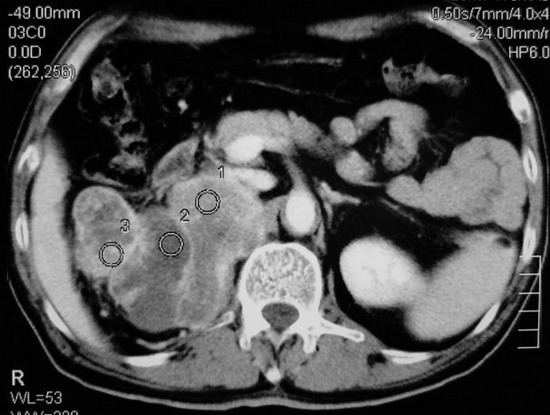

以下是引用杀毒软件在2008-11-17 19:15:00的发言:[br]考虑------右肾癌合并肾静脉---同侧肾上腺受侵可能性大

以下是引用zjzjr在2008-11-17 20:45:00的发言:[br]考虑------右肾癌合并肾静脉---同侧肾上腺受侵可能性大及腹膜后淋巴结转移.